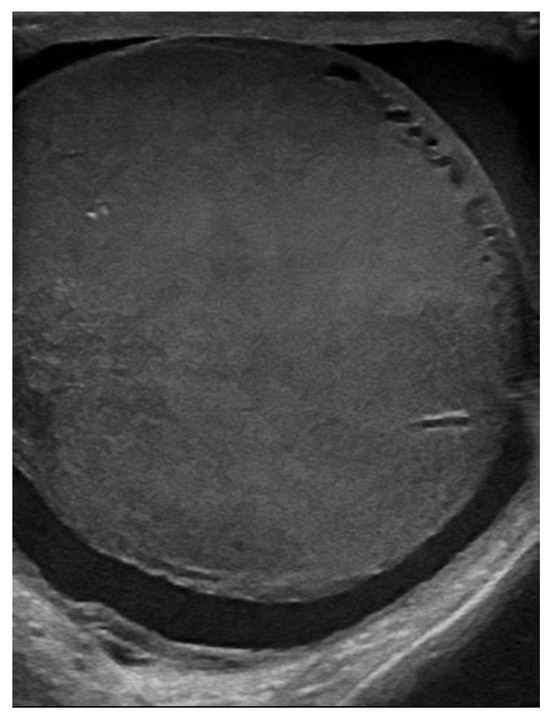

| June 2022 | first extramedullary relapse left testicular—diagnostic immunophenotyping of semen | HyperCVAD Block A radiotherapy, 24 gy/12 sessions for the scrotal sac and the lymph nodes along the left spermatic vein result: complete metabolic remission petct |